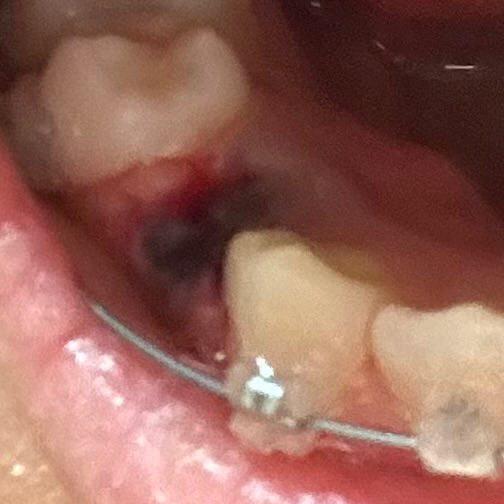

교정 발치 후 출혈 관련 질문이요!!

발치는 3/21 어제 했는데 아직까지 피가 나와서요 ㅜㅜ

근데 양은 많지 않고 그냥 주변에 좀 묻어나는? 그런 느낌이에요 원래 이런건가요??

그리고 잘 낫고 있는지도 봐주시묜 감사하겠습니다!

• 1번 째 사진

현재 사진으로 보아서는 특별한 문제는 없어 보입니다. 출혈 양상은 조금씩 나타날 수 있으며 조금 불편하다면 다시 압박 지혈을 해주는 것이 도움이 될 수 있습니다. 시간이 지나면 자연스럽게 지혈이 될 것으로 보입니다.